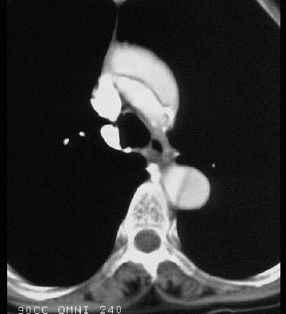

男,64岁,突感胸部剧痛2h,呈撕裂样,并向背部放射,有高血压病史10年,含服硝酸甘油3片不能缓解,CT检查如图所示。首先应考虑的诊断是 ( ) XN-09481.jpg XN-09482.jpg XN-09483.jpg

• A.主动脉夹层